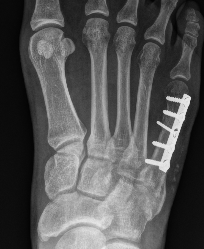

Options

Intramedullary screw

Plate fixation

- systematic review of 10 studies and 300 patients

- screw versus plate

- no difference in outcomes or complications